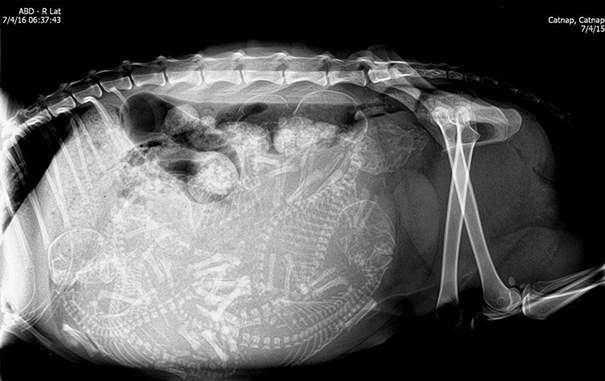

▼肚子裡滿滿的貓咪寶寶

圖片來自:boredpanda